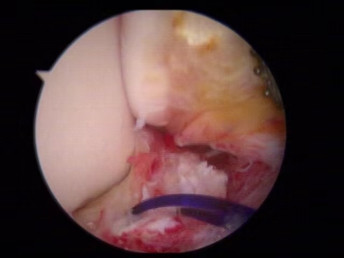

醫(yī)生們在手術(shù)中發(fā)現(xiàn),李先生的右踝關(guān)節(jié)軟骨損傷明顯,踝關(guān)節(jié)前方及內(nèi)外側(cè)均有不同程度的骨質(zhì)增生,相互撞擊引起疼痛,同時(shí)距腓前及跟腓韌帶斷裂。手術(shù)醫(yī)生利用磨鉆,小心翼翼將引起撞擊的骨刺一一去除,然后,修復(fù)了損傷的關(guān)節(jié)軟骨,最后,為他完成了距腓前和跟腓韌帶的修復(fù)。

修復(fù)斷裂的韌帶